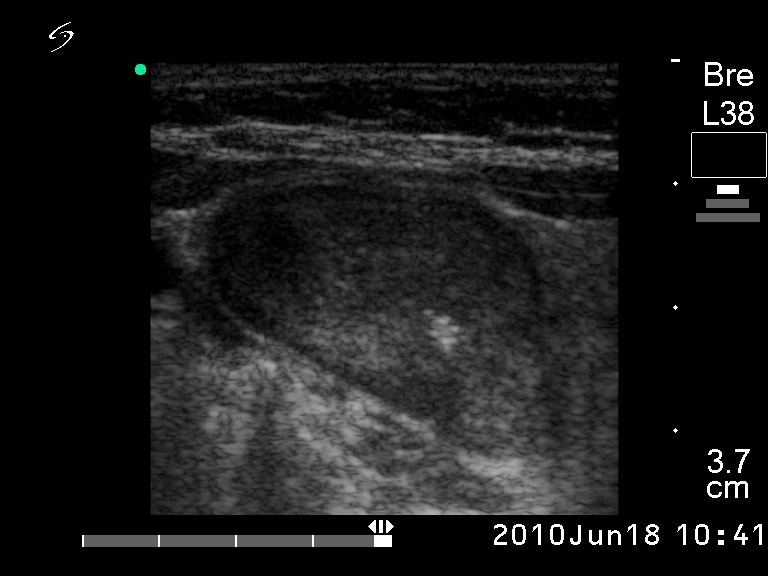

Ultrasonography: revealed a solitary hypoechogenic nodule with halo sign and perinodular blood flow.